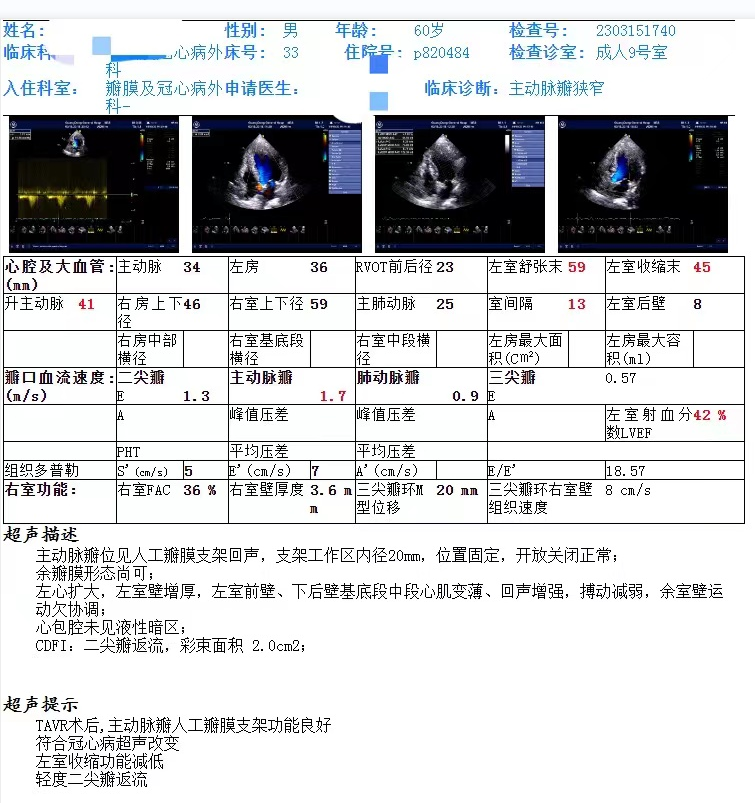

患者为60岁男性,因“活动后胸闷6年、加重1月”入院。2017年于外院行冠脉支架植入,次年于广东省医复查冠脉造影于左回旋支行PTCA;2023年2月下旬再次复查造影,提示LM、LAD内见支架影、管腔通畅,LCx、RCA狭窄。闭塞,由前降至侧枝供应,靶血管细小,无法继续冠脉搭桥。频繁心衰发作,大汗淋漓。

心脏超声:主动脉瓣病变,重度狭窄,开口面积0.70cm²,体表面积2.02 m²,跨瓣血流速度4.38 m/s,平均跨瓣压差46 mmHg,左室射血分数46%。

其他辅助检查:N-型钠尿肽前体 2507.4pg /ml,肌酐97.09 umol/L;心电图见窦律;肺通气功能检查提示轻度限制性通气功能障碍。

TAVR术后,主动脉瓣人工瓣膜支架功能良好